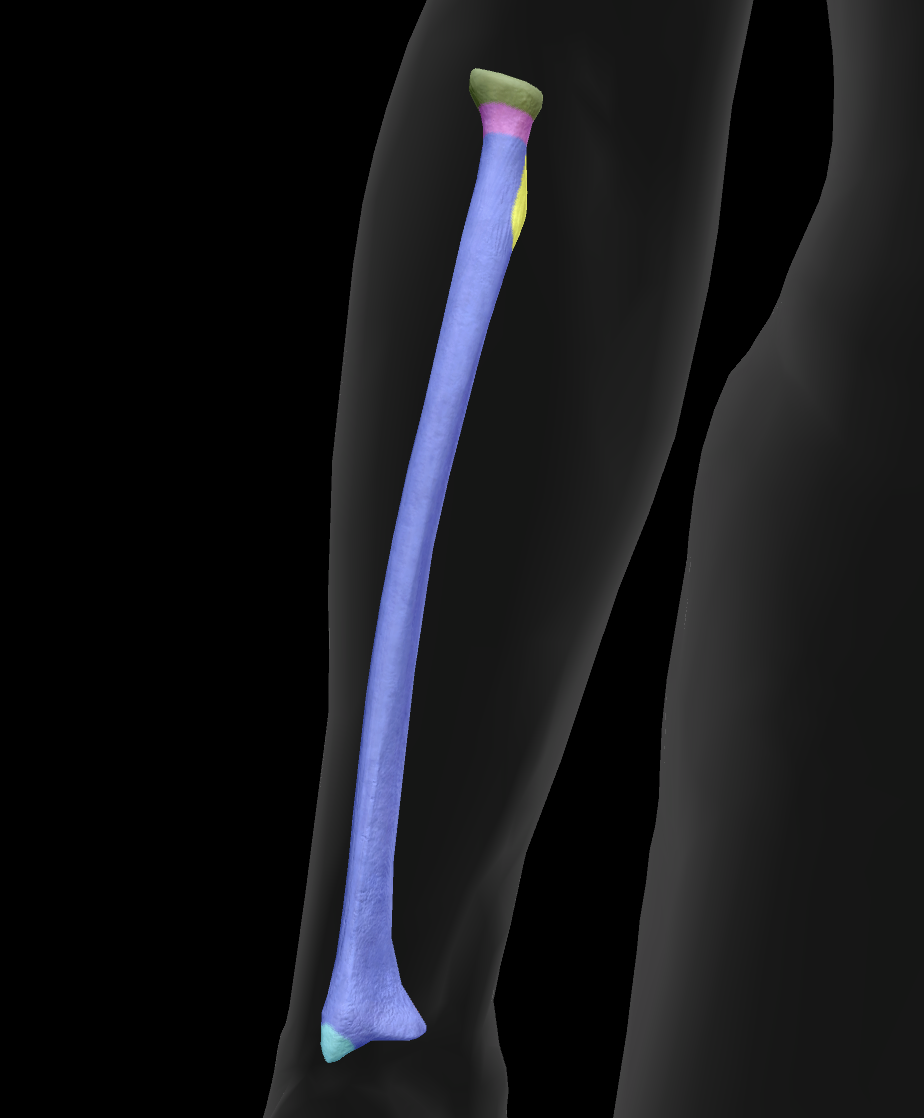

What is this bone?

radius

What is this boney landmark?

head

What is this boney landmark?

neck

What is this boney landmark?

radial tuberosity

What is this boney landmark?

shaft

What is this boney landmark?

radial styloid process

What is this boney landmark?

ulnar notch

What is this boney landmark?

lister’s tubercle